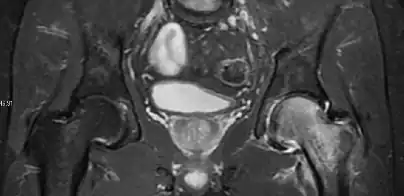

Magnetic resonance imaging

Many pathological conditions of the hip are detected early by MRI due to its high soft tissue resolution and sensitivity. Its accuracy in studying acute hip pain in children has proved to be superior to ultrasound and plan film radiography. However, MRI accessibility and the need of sedation relegate its use to selected cases in which diagnosis is not clear with less demanding techniques. These include differentiating transient synovitis from a septic arthritis or osteomyelitis, diagnosis of inflammatory joint disease or bone tumors, and early detection and follow-up of Perthes disease.[1]

In adults, MRI is currently playing a definite role in the assessment of osteoarthritis. Although traditionally belonging to the arena of radiographs, the role of MRI has been stressed after the term femoral acetabular impingement was coined in 2003. Growing interest has been focused in accurate diagnosis of the acetabular and femoral morphological abnormalities that may lead to early osteoarthritis.[1]

MR imaging is considered paramount to these objectives, mainly when surgery is considered, due to the ability of MRI to portray the whole section of the femoral neck surface, as well as to image the labrum and articular cartilage.[1]

Diagnosis of impingement can only be achieved if, besides imaging findings, there are also clinical symptoms and positive impingement maneuvers.[1]

Most of the angles and measurements described in the plain radiograph section can be accurately reproduced on MRI. In addition, the superiority of MRI resolution with intra-articular contrast allows detection of labral and chondral abnormalities that may influence the choice of medical, percutaneous, or surgical management (Figure 9).[1]

Intra-articular osseous causes of pain include several conditions: avascular necrosis (AVN), transient osteoporosis of the hip (TOH), tumors, and stress or insufficiency fractures. All these entities may present with a pattern of bone marrow edema characterized by decreased signal intensity on T1 weighted images and increased signal intensity on fluid sensitive sequences, such as fat saturated T2-weighted or STIR images. When there is no evidence of a focal lesion associated with the edema pattern, TOH is suspected. When a band of low intensity is seen inside the edematous area, the shape and length of this band become important. It is generally convex to the articular surface in the case of subchondral stress or insufficiency fractures, whereas it is concave, circumscribing all of the necrotic segment, in cases of AVN. When doubts do persist, gadolinium-enhanced MRI tends to show that the proximal portion beyond the band is enhanced in fractures but is not in AVN.[1]